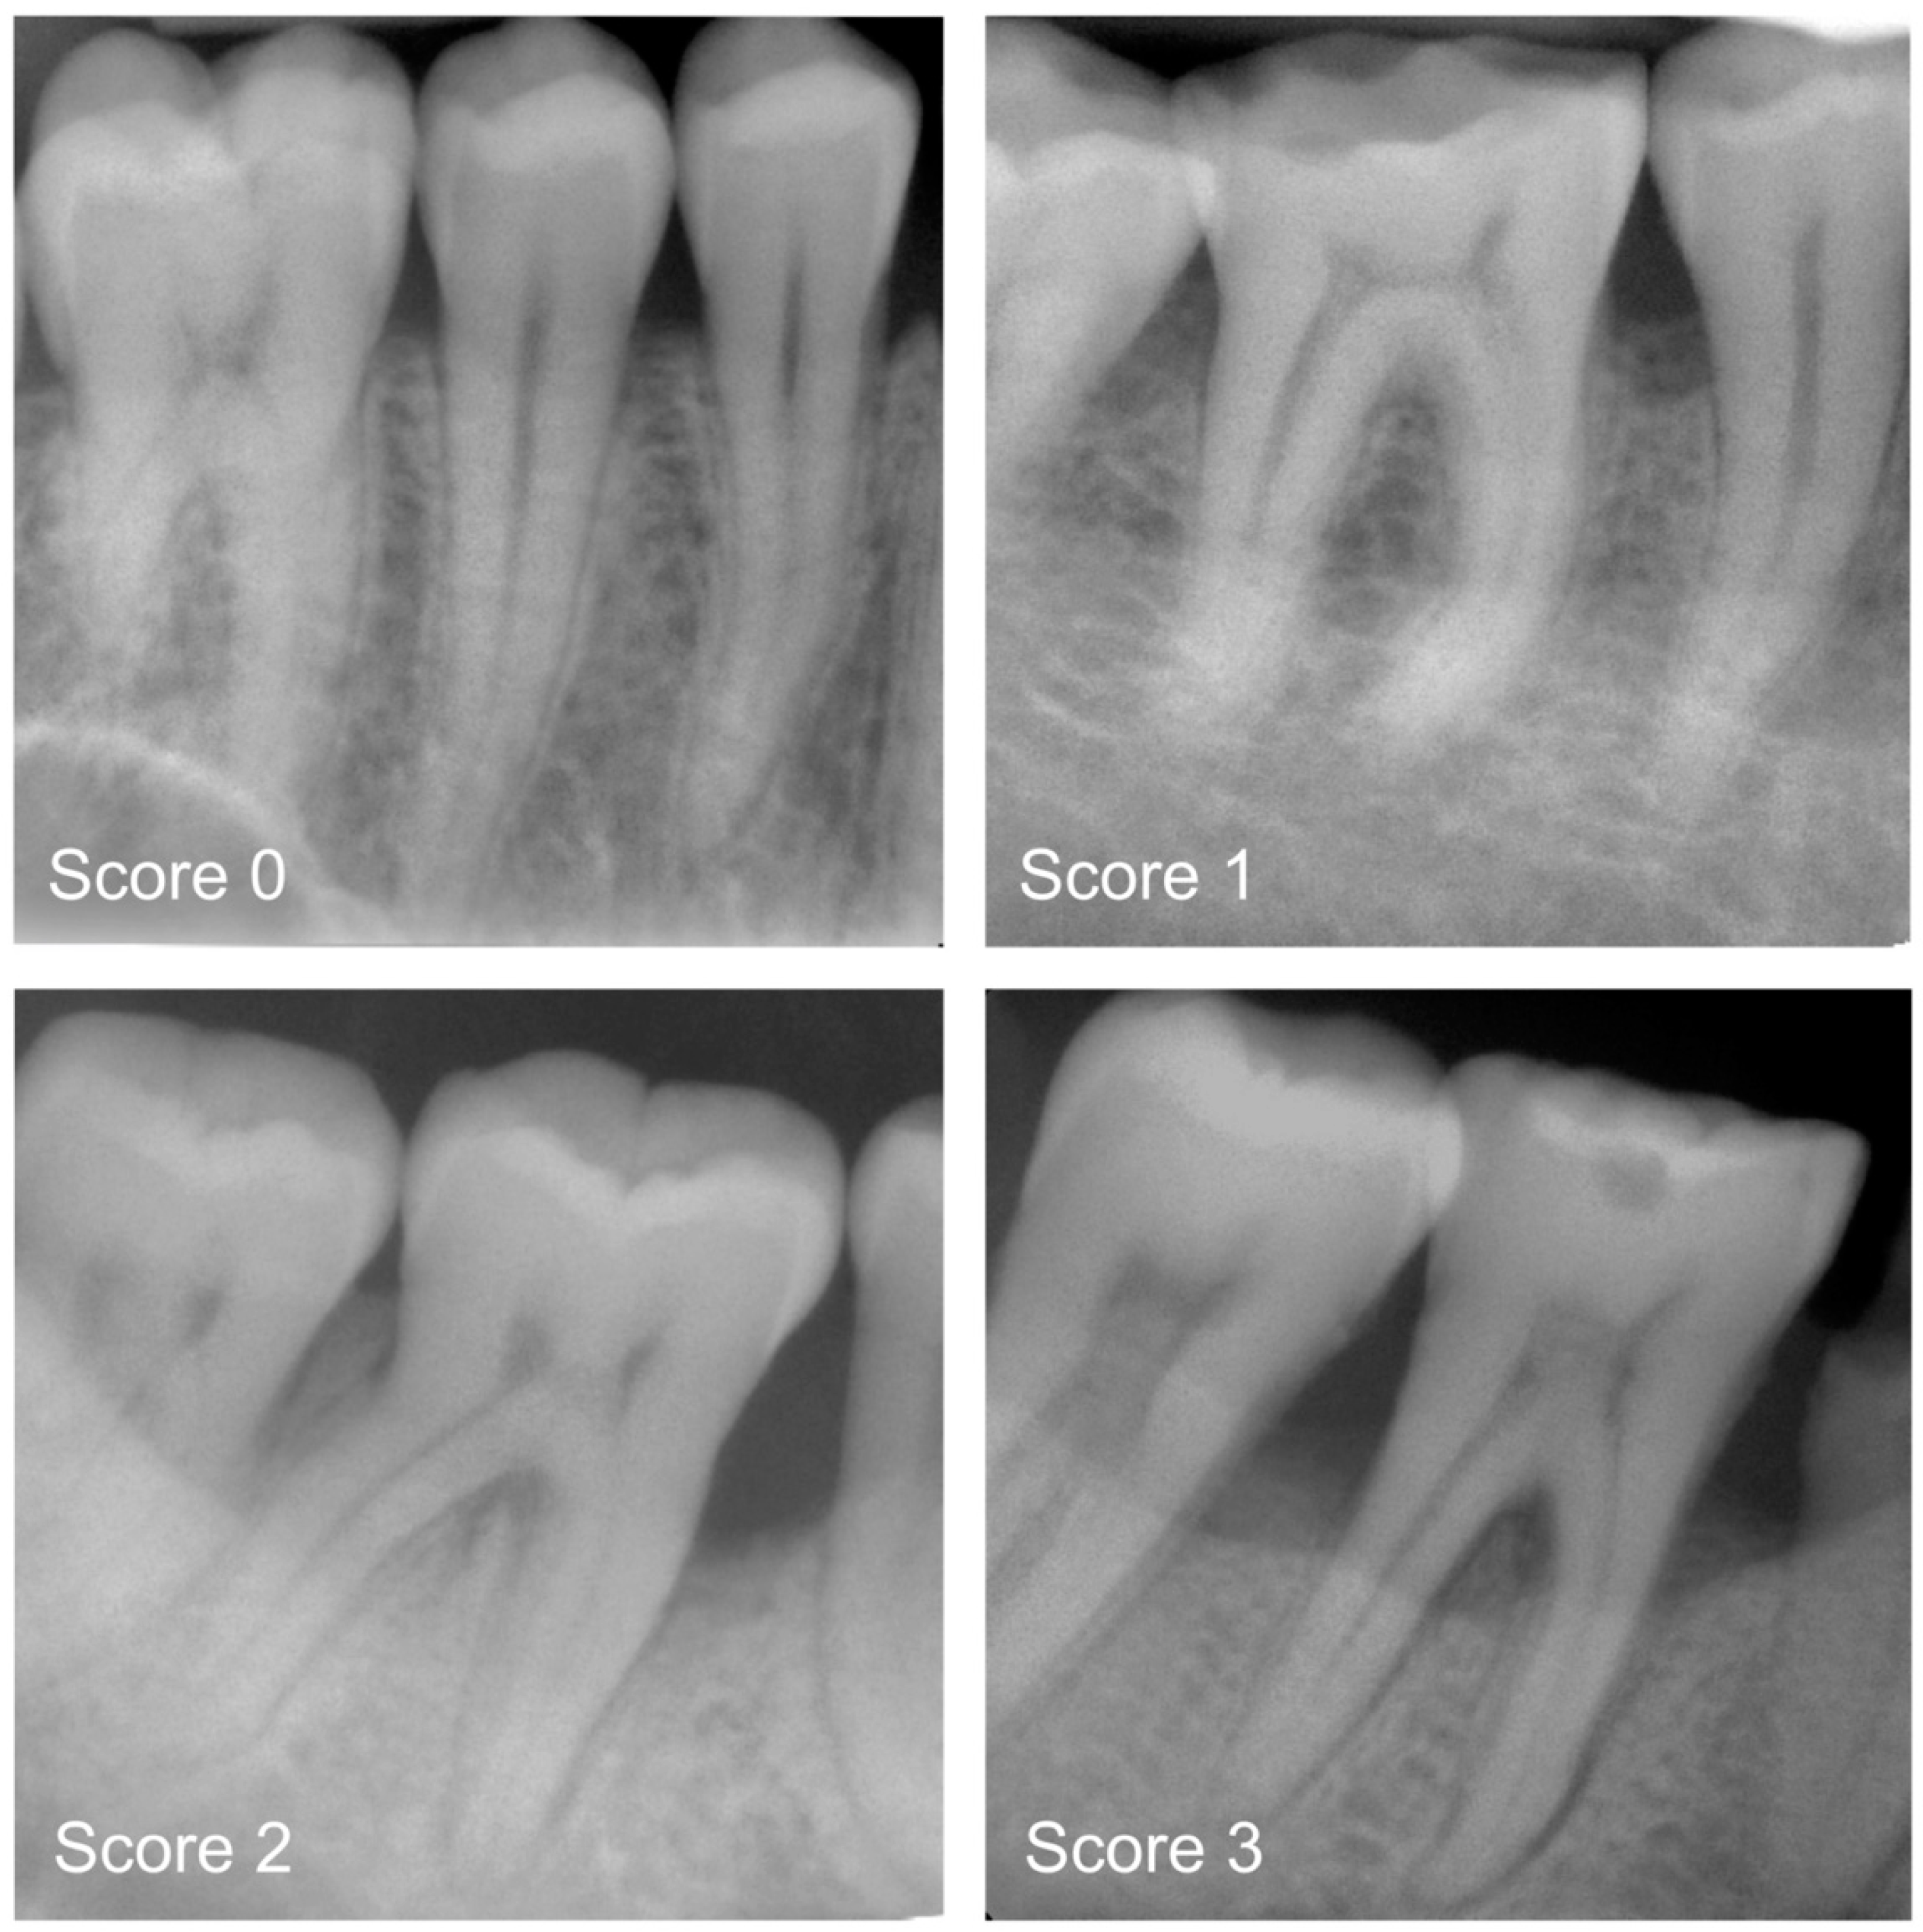

Figure 1.

Examples of periapical radiographs for all categories: healthy periodontium (Score 0), mild radiographic periodontal bone loss (PBL) up to 15% of the root length (Score 1), moderate radiographic PBL between 15% and 33% of the root length (Score 2), and severe radiographic PBL extending to the mid–third of the root and beyond (Score 3).

All radiographs were precategorised by a group of graduate dentists (P.H., T.M., A.W. and L.M.) and later independently counterchecked by experienced examiners (H.D., U.W. and J.K.). For each of the periapical radiographs, a diagnosis was made by differentiating between healthy teeth and teeth affected by mild, moderate or severe PBL [7,8]. Clinical data were not available prior to decision making. In detail, the following diagnostic criteria were applied: 0—radiographic PBL not detectable; 1—mild radiographic PBL up to 15% of the root length; 2—moderate radiographic PBL between 15% and 33% of the root length; and 3—severe radiographic PBL extending to the mid-third of the root and beyond (Figure 1). In the case of divergent opinions, each radiograph was discussed until consensus was reached. Each dichotomized diagnostic decision (0 versus 1 to 3)—one per image—served as a reference standard for the cyclic training and repeated evaluation of the deep learning-based transformer network.